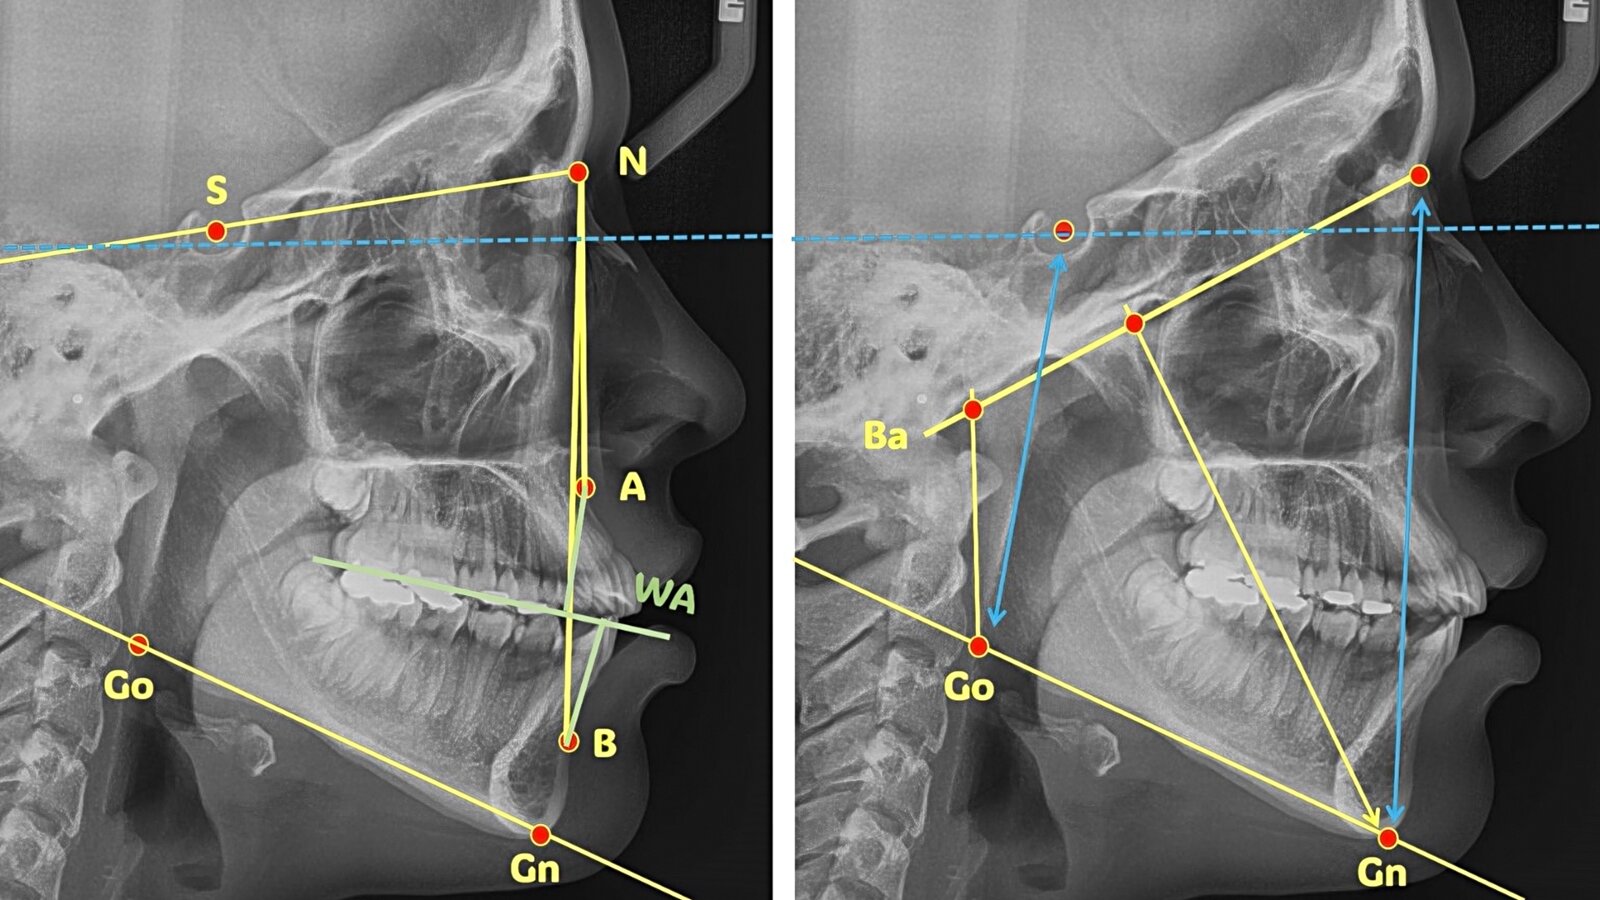

Figura 5. Los métodos basados en aprendizaje profundo podrían permitir la identificación de nuevos puntos de referencia anatómicos para la toma de decisiones clínicas. Foto: Fotos: Servicio de Investigación en Ortodoncia de la Universidad de Santiago de Compostela.

Los autores reivindican la cefalometría como una técnica diagnóstica de gran relevancia en la toma de decisiones clínicas y explican las preguntas que debe responder.